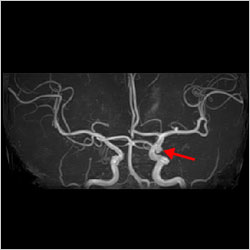

脳動脈瘤

未破裂の脳動脈瘤の発見率は0.4~9.0%と報告されており、発見された場合は必ず経過観察が必要であり、大きさや形状、部位などによっては治療を検討すべき場合があります。